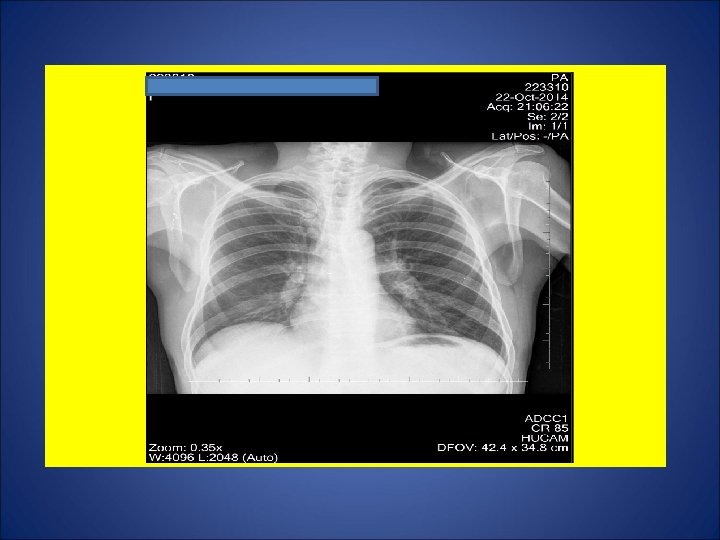

CASO 3, feminina, 25 anos de idade, agente administrativa numa creche. Tosse discreta não produtiva durante os dois últimos meses. Há 1 mês, adinamia. Há 1 semana, febre e sudorese. Durante os últimos 15 dias, perda de 5 Kg. Na madrugada de 09 julho 2014, acordou com tosse seguida de vários episódios de hemoptise. Avaliada por um otorrinolaringologista, sendo prescrito antibiótico 1 cp/dia por 5 dias. Remissão gradual da hemoptise durante os próximos dias. Persistência de tosse discreta. A partir de 21 set 14, surgimento de dor de garganta e disfonia. Negou episódios de escarros hemoptóicos ou hemoptise. A partir de 8 out 14, recidiva da tosse seguida de vários episódios de hemoptise. Foi referenciada para pneumologista, sendo solicitado radiografia de tórax e pesquisa de bacilos álcool ácido resistentes. Negou contato com casos de tuberculose. Negou tuberculose prévia. Negou tabagismo e etilismo. HIV negativa. Ex. fisico: P=73 Kg, Altura= 1, 63 m, IMC= 27, 47, FC = 110 bpm. Tem marca de BCG em MSD.

ESCARROS ESPONT NEOS: 1º) 17/10/14: 10 m. L – MUCOPURULENTO – 10 min: BAC 1+ – CULT em curso 2º) 20/10/14: 10 m. L – SALIVA – 20 min: BAC NEG – TRM M. tuberculosis - CULT em curso 3º) 20/10/14: 10 m. L – SALIVA – 15 min: BAC 2+ – CULT em curso 4º) 21/10/14: 12 m. L – MUCOPURULENTO – 30 min: BAC NEG – CULT em curso